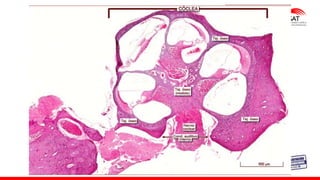

La cóclea es un tubo ligeramente cónico

enrollado sobre sí mismo en 2 1/2 vueltas,

de aspecto muy similar al de un caracol,

su longitud total aproximadamente es de

32 - 35 mm.

COCLEA

Lámina ósea espiral:contiene vasos sanguineos y el ganglio espiral,la

porción coclear del nervio vestibulococlear.

OIDO INTERNO,GANGLIO ESPIRAL

Axones del órgano de Corti tienen sus cuerpos celulares en el ganglio espiral.

Conducto coclear

Rampa

vestibular

llena de Perilinfa

CONDUCTO

COCLEAR

O

Rampa media

lleno de Endolinfa

Timpánica

Rampa vestibular